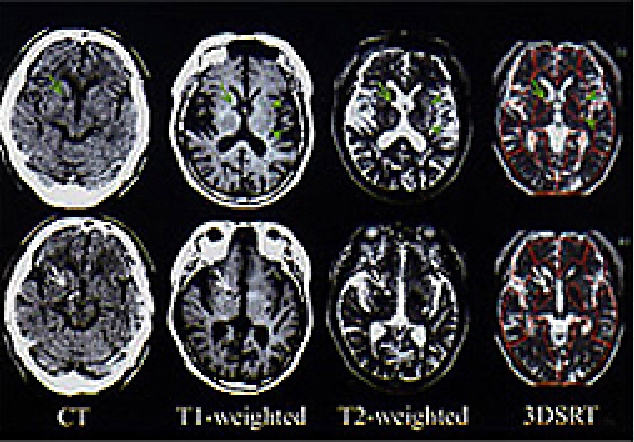

最近は、機能面での画像化に優れるSPECT画像と解剖学的な位置表示に正確なX線CTまたはMRI画像を重ね合わせて、さらに有益な情報を得るようにすることも可能となりました。